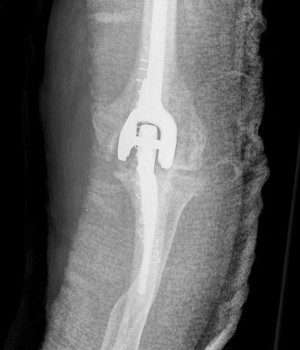

Total Elbow Replacement

A surgical procedure performed to replace worn joint surfaces in the elbow, usually due to severe arthritis. An incision is made to access the joint and the worn surfaces are removed. Artificial components with stems are then cemented into the canals of the ulna and humerus. The components fit together and create a metal and plastic hinge at the joint. When all of the components are in place the elbow is checked to ensure appropriate range of motion, alignment, and stability.

An incision is made at the back of the elbow and the worn surfaces are removed. Replacement stems are placed into both the ulna and the humerus and secured with cement.

What are the implants made of in a total elbow arthroplasty?